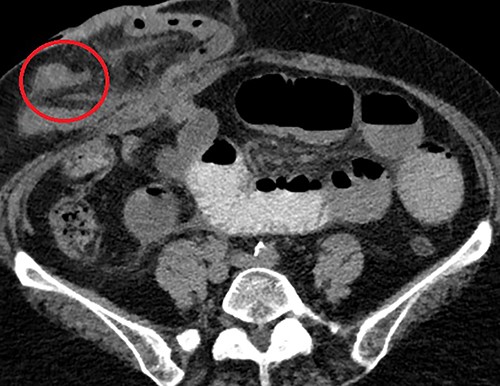

We present a 71-year-old female admitted to a tertiary hospital for an elective repair of a parastomal hernia (loop ileostomy) for recurrent obstructive symptoms. Her background history was only significant for a severe long-standing colitis which necessitated defunctioning ileostomy 3 years prior. On examination, she had a partially reducible parastomal hernia containing loops of small bowel, confirmed on preoperative computed tomography (CT) imaging (Fig. 1).

Axial CT scan with oral contrast demonstrating right-sided parastomal hernia containing small bowel loops (arrow) and proximal small bowel dilatation (asterisk).